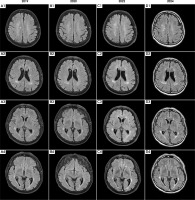

Figure III

Time evolution of magnetic resonance imaging (MRI) abnormalities. Axial projection; T2-weighted sequences (2019, 2020, 2022) and fluid-attenuated inversion recovery (FLAIR) sequence (2024). The MRI scan performed in 2019 during the patient’s initial visit, along with follow-up MRIs in 2020, 2022, and the latest in 2024, are shown. In 2019 (A1-4), multiple, poorly demarcated supratentorial hyperintensities were observed bilaterally in the deep white matter and periventricular areas. The lesions did not become enhanced after contrast and showed no diffusion restriction. As shown in the follow-up MRI scans from 2020 (B1-4), 2022 (C1-4), and 2024 (D1-4), despite acute and maintenance treatment being initiated and a regression of ophthalmological symptoms, the lesions exhibited minimal temporal evolution throughout the follow-up period. No new lesions appeared between subsequent hospitalizations